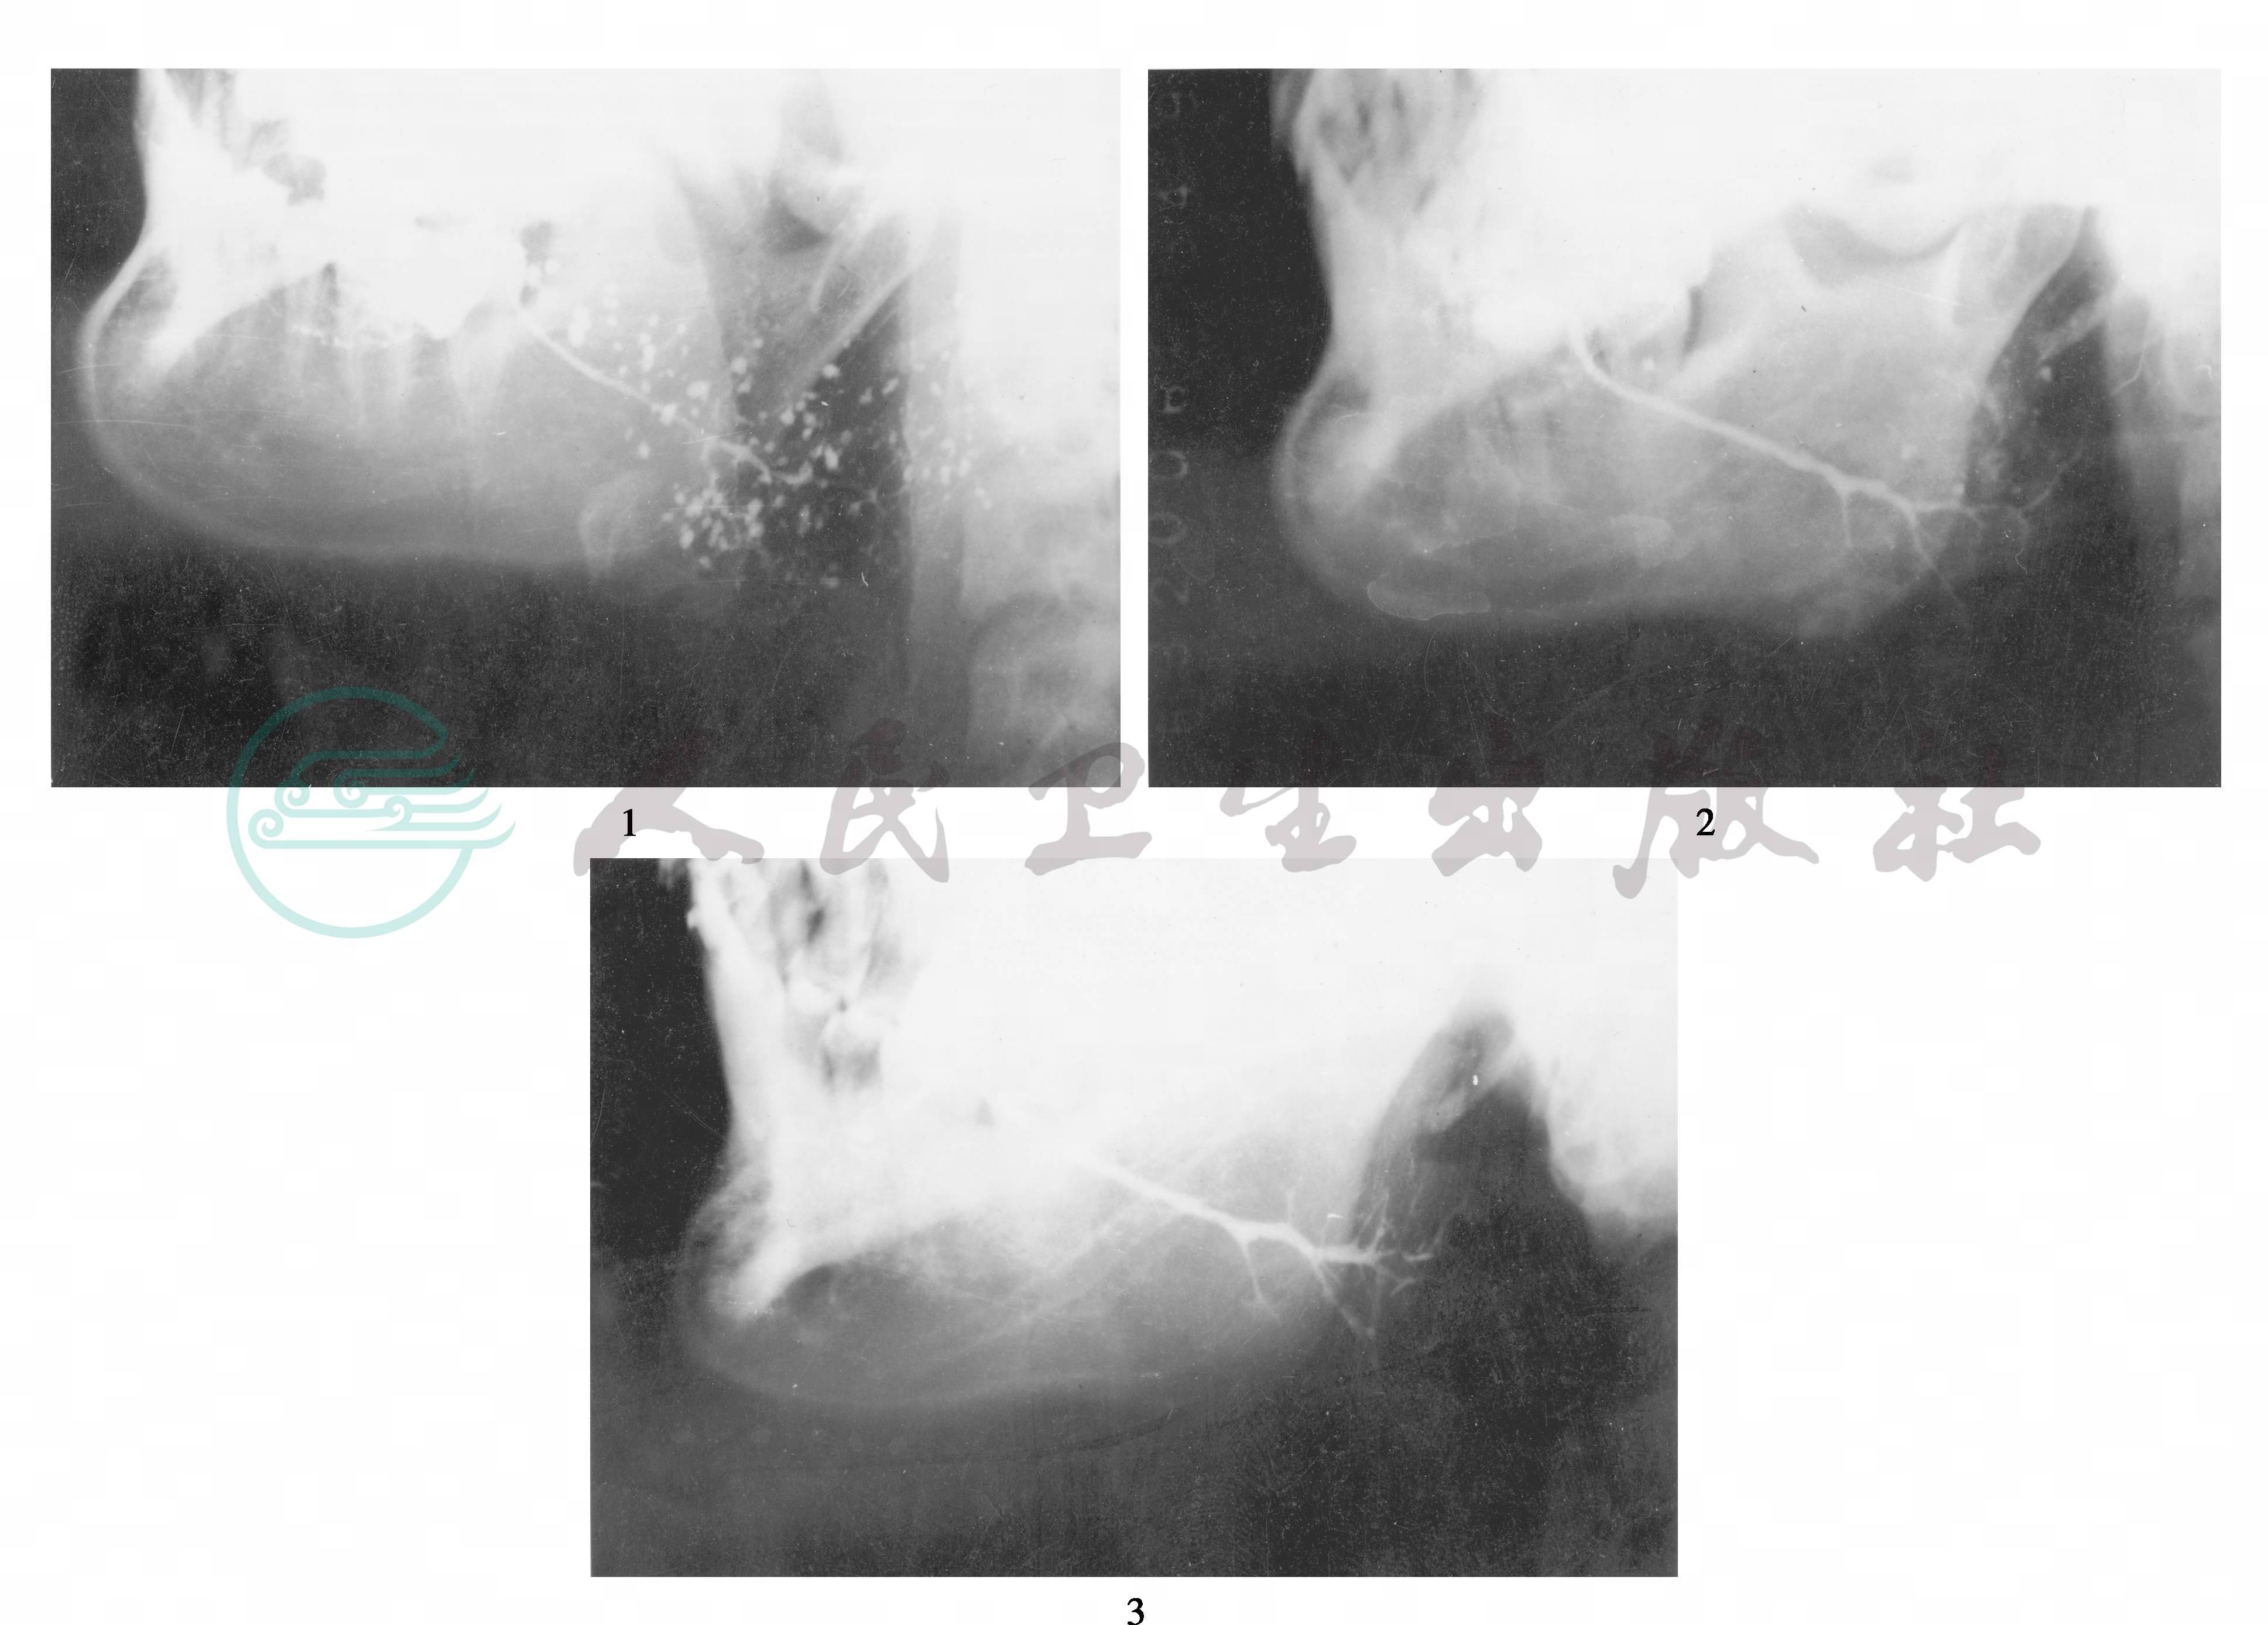

腮腺造影的表现类似于儿童复发性腮腺炎,但有部分患者可痊愈,X线片上点扩完全消失。部分患者明显好转,X线片上点扩数减少50%以上 (图1)。

图1 儿童复发性腮腺炎延至成人复发性腮腺炎后逐渐痊愈

1.女,出生后100天开始双腮腺反复肿胀,15岁时造影,有大量“点、球扩”2.同一患者35岁,右腮腺反复肿胀两次,右腮腺造影仍有散在“点、球扩”3.同一患者,38岁,造影显示已痊愈